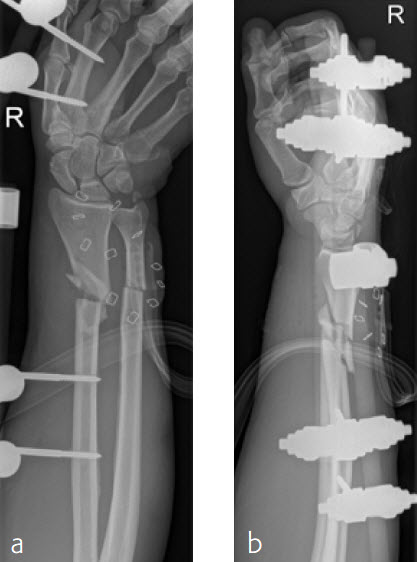

Case 4: Open radius shaft fracture

A 59-year-old farmer suffered a crush injury with an open forearm fracture (AO22 C2, Gustilo and Anderson IIIB) (Fig 1). Initial stabilization was carried out by external fixator (Fig 2). After four rounds of debridement and capillary ingrowth of a splitting skin graft at day 17, the VA LCP Extra Long Two-Column plate was used for fixation of the radius. A 2.7 mm LCP Condylar Plate was used for fixation of the ulna. The plates provided good stability for a functional after-treatment.

At the 3-month follow-up, the patient was full weight bearing with healing fractures (Fig 3).